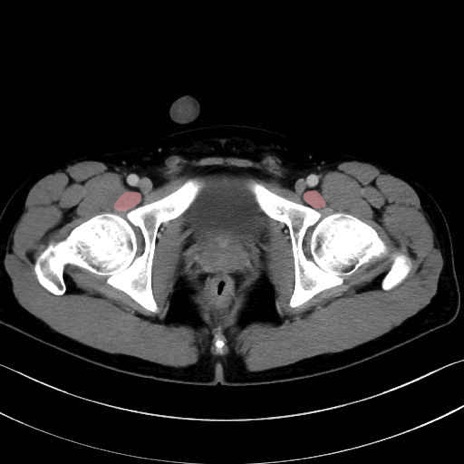

4. 深層外旋六筋(股関節の深部)

梨状筋 (Piriformis)

内閉鎖筋 (Obturator internus)